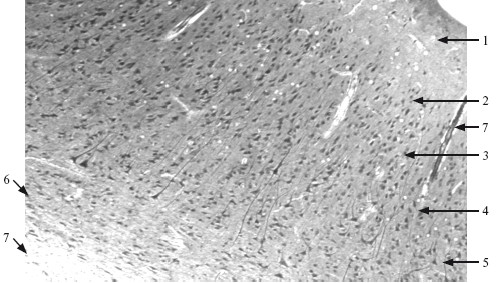

Рис. 9.3. Кора полушарий большого мозга. ×66.

1 – молекулярный слой; 2 – наружный зернистый слой; 3 – наружный пирамидный слой; 4 – внутренний зернистый слой; 5 – внутренний пирамидный слой; 6 – полиморфный слой; 7 – мягкая мозговая оболочка.

Цитоархитектоника коры. Все области коры головного мозга человека построены по единому принципу и состоят из шести основных пластинок (слоев):

I – молекулярная пластинка. Характеризуется незначительным количеством мелких нейроцитов, называемых горизонтальными клетками Кахаля;

II – наружная зернистая пластинка. В ней значительное количество небольших звездчатых нейроцитов и малых пирамидных нейроцитов;

III – наружная пирамидная пластинка. Состоит из малых, средних и больших пирамидных нейроцитов. Величина клеток возрастает по направлению к белому веществу: на самой поверхности – малые пирамидные, в глубоких слоях – большие;

IV – внутренняя зернистая пластинка. Состоит из большого количества звездчатых нейроцитов и мелких пирамидных нейронов;

V – внутренняя пирамидная пластинка. Характеризуется наличием больших пирамидных нейроцитов. В корковом отделе двигательного анализатора обнаруживаются гигантские пирамидные нейроциты, описанные впервые В. А. Бецом. Аксоны этих клеток образуют пирамидные пути;

VI – мультиформная пластинка. Состоит из нейроцитов трех разновидностей: звездчатых, веретеновидных и клеток Мартинотти.